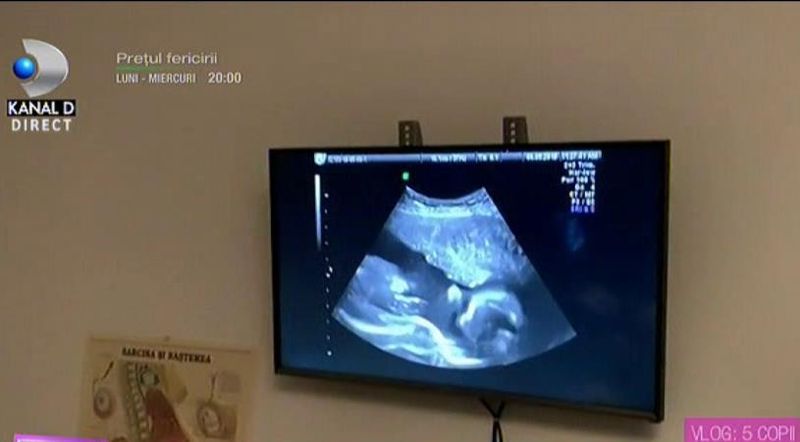

Anca Serea și Adi Sînă au filmat momentul în care au mers la ecografie și au văzut-o pe micuța Leah.

Anca Serea a avut mari emoții înainte de a ajunge la clinică și a o vedea pe monitor pe bebelușa din burtică, cel de-al șaselea copil al său.

Emoționată, dar fericită, Anca Serea a răsuflat ușurată atunci când a aflat că totul este în regulă cu fetița ei, care va primi numele Leah.

"Seamănă cu Ava și cu frații ei. Uite ce năsuc are! Mami e foarte fericită, avea mari emoții. Totul e bine, o să venim la consultație peste o lună. Până atunci trebuie să fim fete cumințele", a spus Anca Serea în vlog.